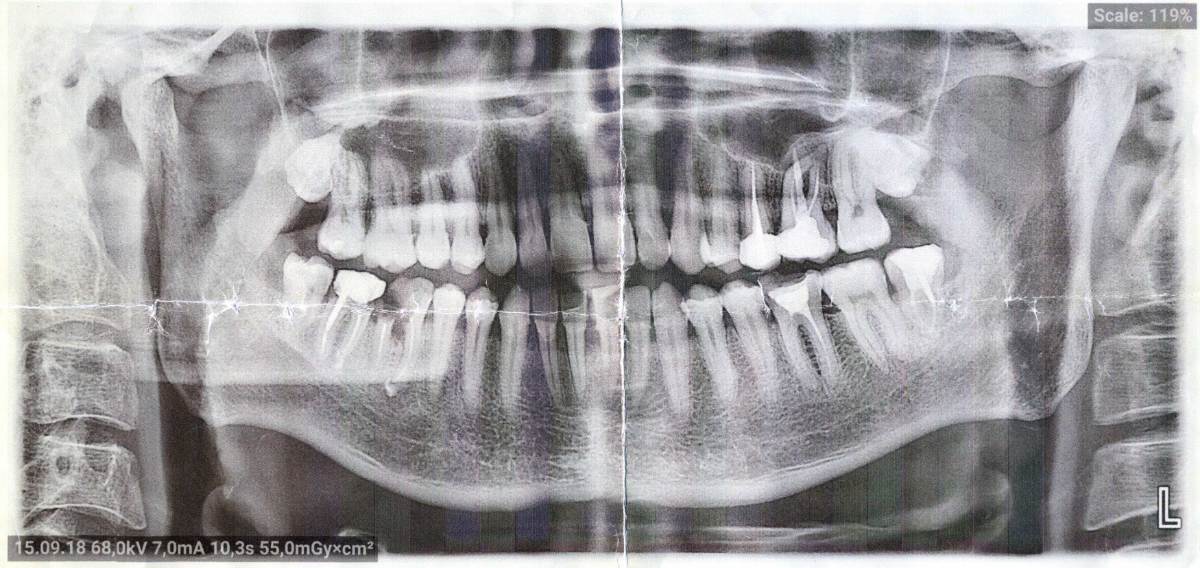

Sergey-010101 Опубликовано 11 октября, 2025 Поделиться Опубликовано 11 октября, 2025 (изменено) Здравствуйте. Можно ли мне пересадить восьмерки сверху на места шестерки и семерки снизу? Сверху по бокам это ведь восьмерки? 2018 г. 2023 г. Изменено 11 октября, 2025 пользователем Sergey-010101 Ссылка на комментарий

Женька Опубликовано 12 октября, 2025 Поделиться Опубликовано 12 октября, 2025 (изменено) @Sergey-010101 потому что зубов у Вас уже давно нет. И в Вашем случае трансплантация зубов намного сложнее технически, чем имплантация. Добавьте к этому возможную потерю ширины костной ткани (которую мы не можем оценить по данным снимкам). А те кто умеют даже в таких условиях трансплантировать зубы, как правило находятся в гораздо более высокой ценовой категории, чем в среднем по рынку. Я бы рассматривал обычную имплантацию в Вашем случае и не старался придумать велосипед. Даже если очень хочется. Даже если говорят, что дешевле. Даже, если говорят, что лучше чем имплантация. Изменено 12 октября, 2025 пользователем Женька 1 1 Ссылка на комментарий

red_butler Опубликовано 13 октября, 2025 Поделиться Опубликовано 13 октября, 2025 Здравствуйте Sergey-010101, сделайте Кт 1 Ссылка на комментарий